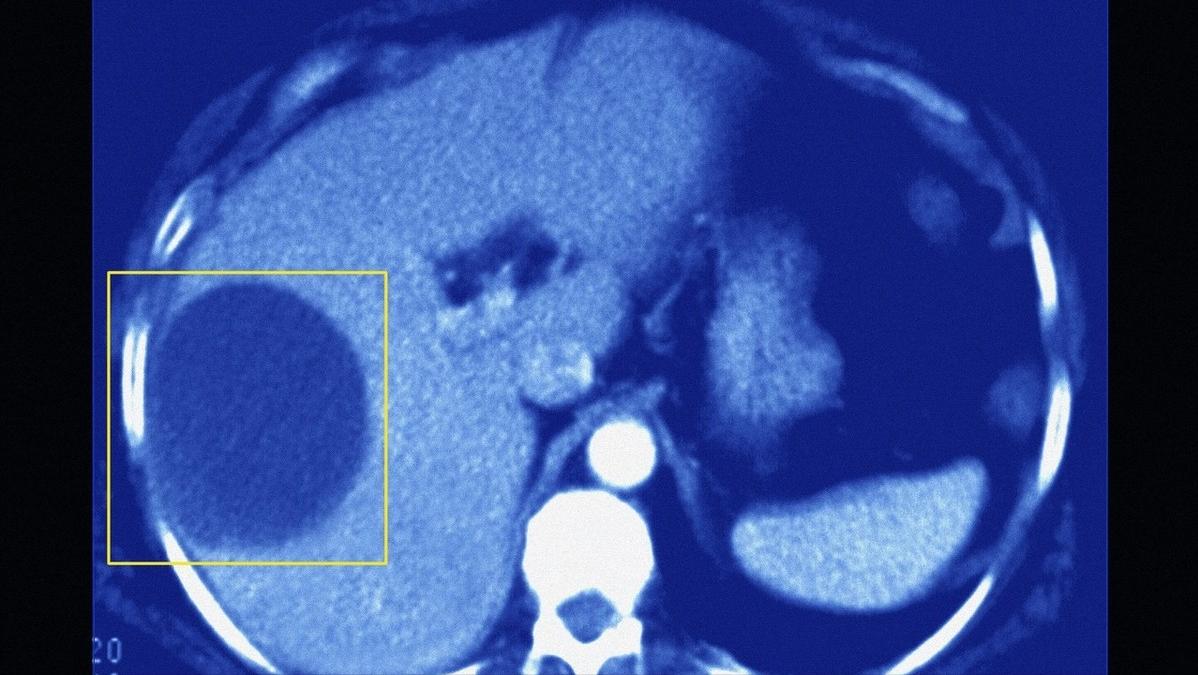

肝囊肿是一种相对常见的肝脏良性占位性病变,大多数时间都处于“静止状态”,而且生长缓慢,不过在肝内生长部位没有规律可循,可单发、多发。

一般情况下,肝囊肿呈现球形,外层是纤维性囊壁,囊壁光滑,且肝囊肿体积一般直径仅有1~2cm,有的可达10~20cm,内部充满了囊液,所以肝囊肿又被称为“肝水泡”。